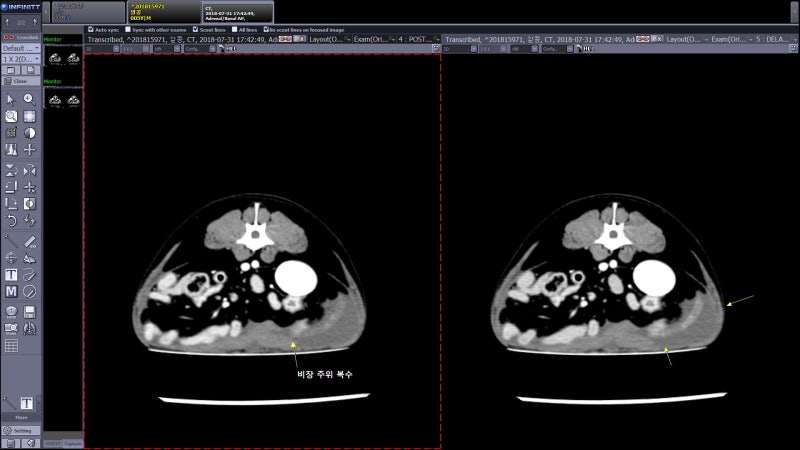

CT 검사를 통한 비장 파열의 진단, 응급 수술 : 네이버 블로그